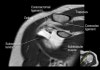

- Axial section

1) Anterior & posterior labrum

2) Subscapularis muscle & tendon

3) Biceps long head tendon

4) GH joint cartilage

5) Osseous structure

6) 관절액 있을때 FSE T2 FS에서 Labrum 선명, 관절액 없을때 FSE PD FS에서 Labrum 선명